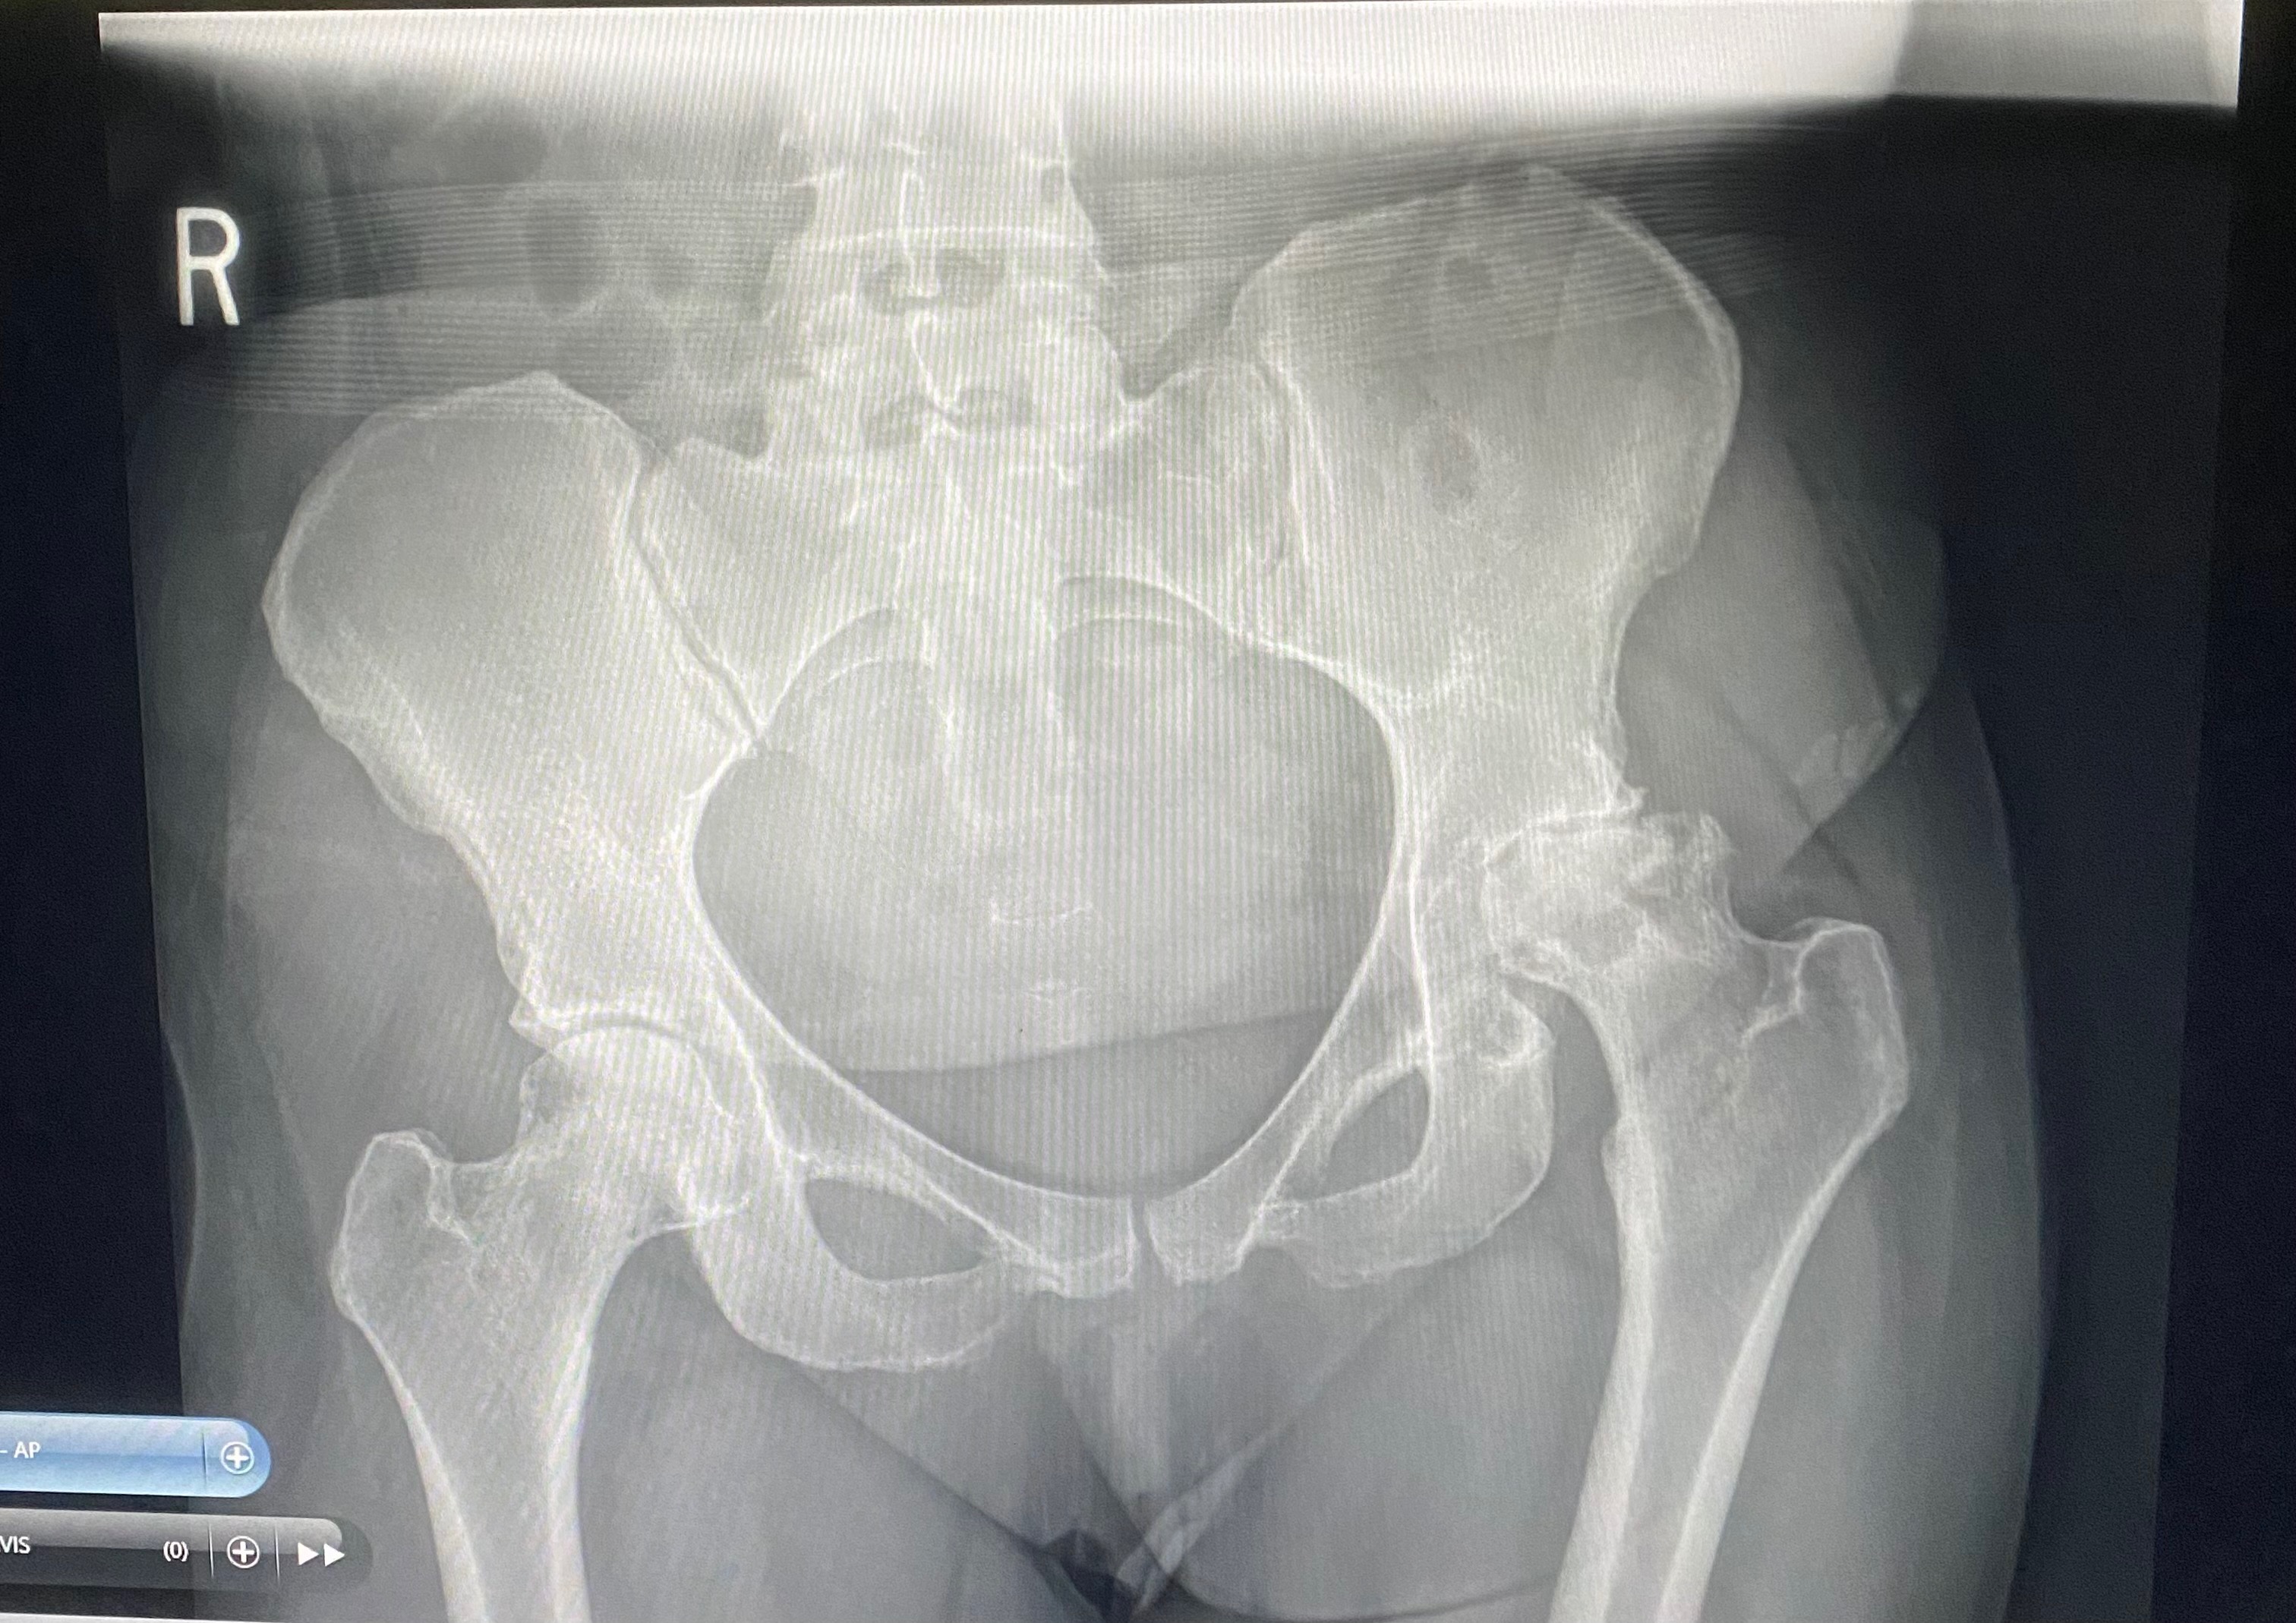

I’ve always had back and hip issues, but I just attributed it to constantly being on my feet 6-12 hours a day, 5-6 days a week; until September 17th when I was officially diagnosed with Avascular Necrosis in my hips. Essentially, both of my hips were not getting any blood supply, causing the bone in my hip joints to die and erode away. It’s extremely painful but, without insurance, all I could do is continue to work and hope that I’d be able to find affordable insurance soon. While my jobs have been as accommodating to me as possible, nobody could have prevented the inevitable.

Sunday, December 7th, I took myself to the ER after trying and failing to get another work day started. I couldn’t take more than 4-5 steps without bursting into tears and after a CT scan was preformed, I learned why. Not only has my left hip eroded almost entirely, my right hip bone was completely hollow inside, causing it to break at least a week or two prior. I had no choice: it was time for surgery, whether I had the insurance or not.